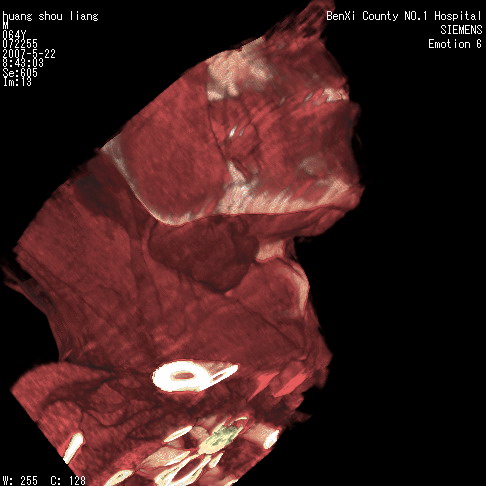

男性,64岁。颈部包块8年。最近增大。

对不起大家,可能是片子发太多有点乱,正常腮腺在下颌角的外侧,颌下腺在下颌体的中部内侧,本例在下颌角内侧偏下,和腺体一点关系都没有,从vrt和mpr上可以很明显看出来,再者肿块是好多粘连在一块的,大家在仔细看看,左侧可能也是吧,我还是考虑为肿大的淋巴结融合在一块,但性质??????

右侧腮腺下部均匀软组织密度肿块,外形不规则,与周围组织分界清晰,考虑右侧腮腺混合瘤或多形性腺瘤。

大家好,病理结果出来了,如大家所说,颌下腺混合瘤。

唉,解剖没学好吧,我诊断错了,不过还是有些不理解回去我在多看看书,谢谢大家的参与,以后我还会奉献好的病例。